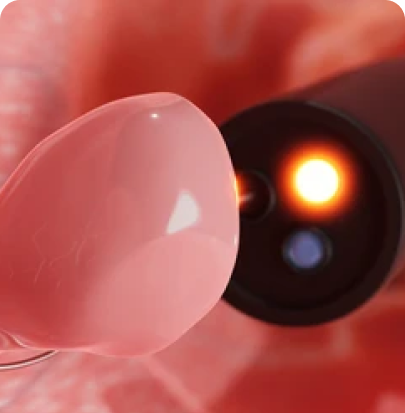

Endoscopic Anorectal Surgery is a minimally invasive surgical procedure used to treat conditions affecting the anus and rectum, such as hemorrhoids, anal fissures, or rectal prolapse. This technique uses an endoscope, a thin, flexible tube with a camera, which allows the surgeon to view the affected area on a monitor

Endoscopic Thyroid Surgery begins with a detailed pre-operative assessment, including imaging and fine-needle aspiration cytology if required. The surgery is typically performed under general anaesthesia. Small incisions are made in inconspicuous areas like the axilla, chest, or behind the ear, through which a high-definition endoscope and specialized instruments are introduced. The surgeon carefully excises the targeted thyroid tissue while monitoring critical structures such as the recurrent laryngeal nerve and parathyroid glands. The removed tissue is sent for histopathological analysis. The procedure concludes with meticulous closure of the incisions, ensuring optimal healing and minimal scarring.